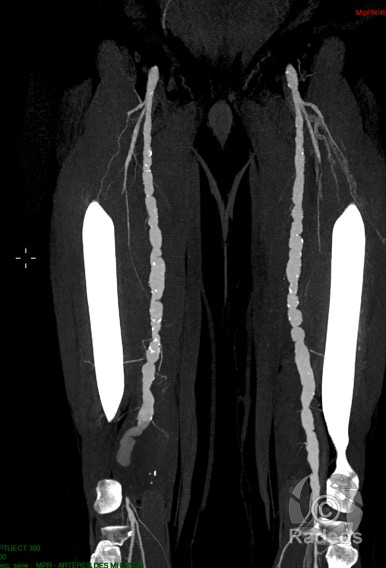

HOTCASE

Trouvez le diagnostic du cas du jour